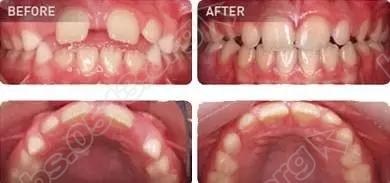

牙博士矫正真人案例

640.webp (2).jpg

640.webp (3).jpg

640.webp (4).jpg